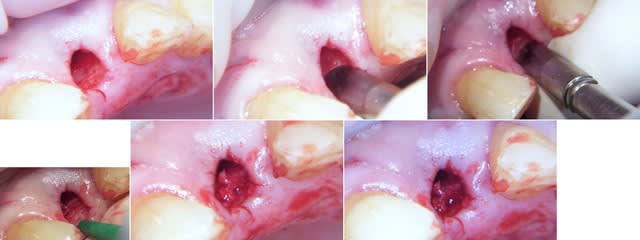

le probleme de depose c'est l'apex de limplant tu risque ça:

xbk